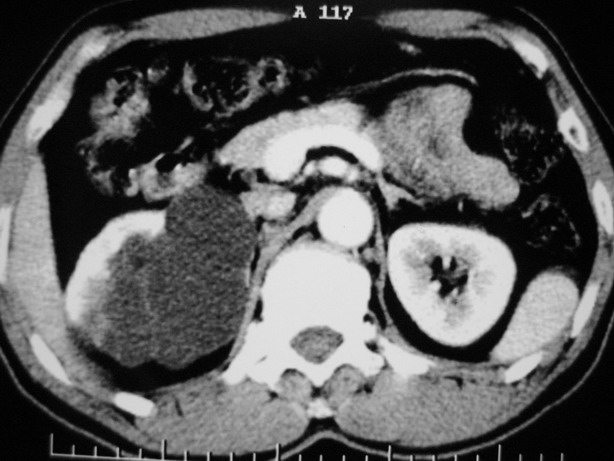

增强:

肾盂旁多囊性占位,有实性成分,增强有轻度强化,收集期病变内无造影剂显影。诊断肾盂旁囊肿,有实性成分无法解释,查书后诊断为:多房性囊性肾瘤!!不知大家同意否?????????对本病知道不多,望大家不吝赐教!!

右肾多发囊性低密度影,囊内有增强的隔及实性组织,考虑囊性肾癌。